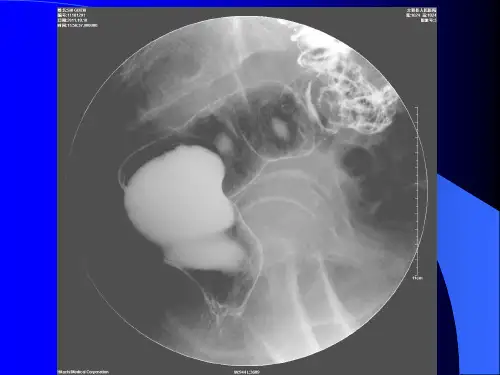

2)充盈缺损 多为向腔内生长,边缘不规则的充盈缺 损。可发生在肠壁一侧,该处肠壁僵硬,结肠袋消 失。肿瘤较大时可阻塞腑管。盲肠部腺癌常表现为 圆形或椭圆形充盈缺损,常合并肠套叠。